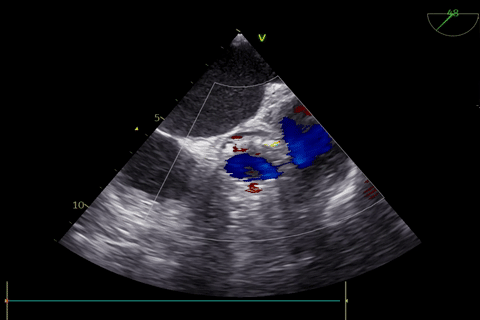

术前超声评估:

主动脉瓣狭窄(重度),收缩期主动脉瓣上流速增快,最大流速约4.5m/s,最大压差约82mmHg,平均流速约3.3m/s,平均压差约49mmHg。左室肥厚,左室舒张功能减低。D-Dimer5.22mg/1FEU,NT-proBNP780.3pg/ml,hsTNI最高270pg/ml,CK-MB最高4.9ng/ml,肌酐56μmol/L,血钾3.7mmol/L。双下肢大动脉超声显示双侧股动脉多发斑块。双侧锁骨下动脉超声未见明显异常。双侧颈动脉超声显示颈动脉内中膜增厚、斑块形成。双下肢深静脉超声显示双下肢深静脉未见血栓。主动脉+腹主动脉+髂动脉CTA:主动脉、髂动脉粥样硬化,主动脉瓣钙化。冠脉造影显示RCA中重度狭窄,于RCA植入支架2枚。